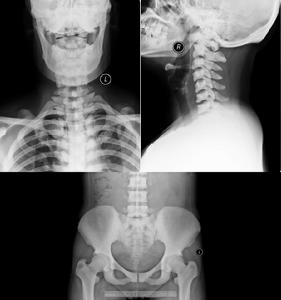

3.氟骨症的X線診斷分型與分度:X線照片要求骨紋顯示清晰,至少包括骨盆及側前壁、小腿正位。

(1)分型:按骨密度和結構的主要改變可分3型:①硬化型:主要有兩種:A.骨密度增高,骨小梁增粗,融合骨皮質增厚,髓腔變窄或消失。B.骨間膜及周圍韌帶骨化。②疏鬆型:亦可分為兩種情況:A.骨密度減低,骨小梁稀疏。骨質有不同程度的吸收脫鈣或造成骨骼變形。B.骨間膜或骨周韌帶骨化。③混合型:兼有以上兩者特點(同時存在不同程度的骨質增生及骨吸收)或松質骨呈網狀或囊狀結構,皮質骨結構鬆散單位面積內骨小梁數目明顯減少。

(2)分度:以上3型中都有不同程度的變化,可分為早期改變及輕、中、重3度。 ①早期改變:有下列徵象之一者可診斷為早期氟骨症:A.長骨骨端、骨盆骨僅見明顯成片的點狀紋理或有增粗紊亂的骨紋。B.四肢長骨皮質緣可出現兩處以上幼芽破土狀骨疣.橈骨脊處多呈波浪狀增生。②輕度:A.骨密度較正常略高,骨小梁粗密,出現骨斑,骨小梁變細,密度減低。B.肌肉韌帶附著處出現尖狀骨化,骨間膜明顯增生。③中度:A.骨密度明顯增高,皮質增厚,骨小梁增粗,部分融合;或有皮質變薄,骨小梁細而稀,密度降低,或骨小梁稀疏,但紋理粗大,密度增高。B.骨間膜及骨周韌帶有較大範圍之骨化。④重度:A.骨小梁增粗,大部分融合成片,髓腔皮質界限不清;或骨質疏鬆呈斑片狀吸收,皮質骨部分中斷消失骨變形較明顯。B.骨間膜及周圍韌帶骨化更明顯,可成橋形,並可出現其他軟組織(如血管)的鈣化影。

1.X線表現

(1)骨質疏鬆型:骨紋理粗而稀疏可為早期氟骨症的惟一表現。

(2)骨軟化症:以脊柱和骨盆明顯,其骨密度減低,紋理模糊。脊椎側彎、駝背。椎體雙凹變形骨盆縮窄畸形和假骨折線形成骨軟化可與骨質疏鬆,骨硬化和軟組織鈣化同時出現,呈混合型。

(3)骨硬化型:骨硬化常發生在脊柱、骨盆肋骨和顱骨。骨紋理粗如麻袋布或礫砂狀,嚴重者骨紋理融合,結構模糊,透X線度低而似象牙。骨硬化常伴四肢骨的骨端骨質疏鬆在顯著鈣攝入不足時可有繼發性甲旁亢此時四肢骨呈纖維囊性骨炎表現。

美國婦女嗜茶成性患罕見骨病